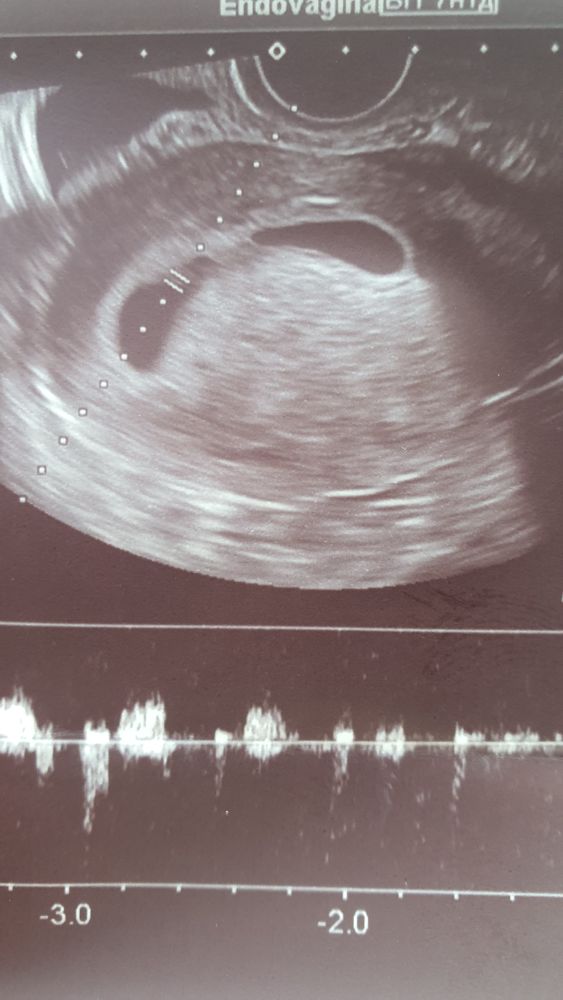

УЗИ, КТГ, доплерДевочки, нужна помощь. Сильный тонус. Была на узи. Б соотв сроку 7 нед, сердцебиение нашли. Долго смотрел меня. Сначала намерял жм 4.2, потом 5.4, потом снова 4.2. На этом остановились. Но сказал, что пя странной формы, что очень сильный тонус, который его сдавил. Первый раз с таким сталкиваюсь. Было у кого такое? Сильно страшно? А то одни говорят, что такого недуга, как тонус не существует, другие наоборот